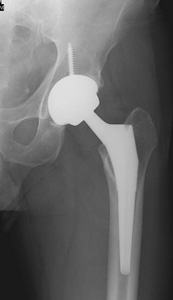

In the older patient, the chance that the head of the femur is damaged in this way is higher. It is generally felt that for these displaced fractures, patients will do better if some of the components of the hip are replaced. In some cases, this can mean a replacement of the ball, or head of the femur (hemiarthroplasty). In other cases, this can mean the replacement of both the ball and socket, or head of the femur and acetabulum (total hip replacement).

Hemiarthroplasty is a type of hip replacement in which only the "ball" of the hip is replaced.

A total hip replacement replaces both the hip socket and ball.